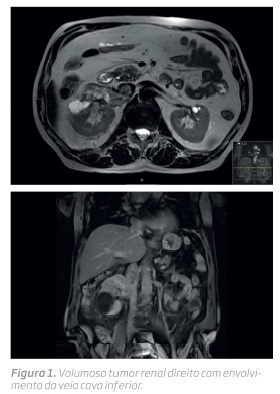

Homem de 75 anos sem antecedentes de relevo foi referenciado à consulta de Urologia por volumosa massa renal direita com extensão à veia cava inferior infrarrenal, observado em ressonância magnética nuclear (RMN) (fig 1). O doente foi proposto para nefrectomia radical e uma vez que apresentava um trombo tumoral na veia renal que se estendia à veia cava inferior foi solicitada a colaboração da Angiologia e Cirurgia Vascular.